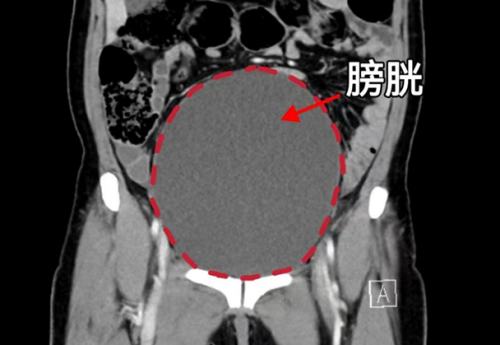

CT显示膀胱高度膨胀、尿道梗阻

。检查发现,其子宫脱垂已导致尿道完全梗阻,膀胱高度膨胀,且脱垂组织因长期摩擦导致严重溃烂、感染,病情危急。

妇产科三区主任魏馨介绍,经检查发现患者为子宫脱垂三度(Ⅳ期),子宫和阴道前后壁完全脱出阴道口,由于脱出的组织压迫尿道,造成尿道梗阻、尿潴留、泌尿系感染,同时还合并有支气管扩张并感染、低蛋白血症、轻度贫血等情况。